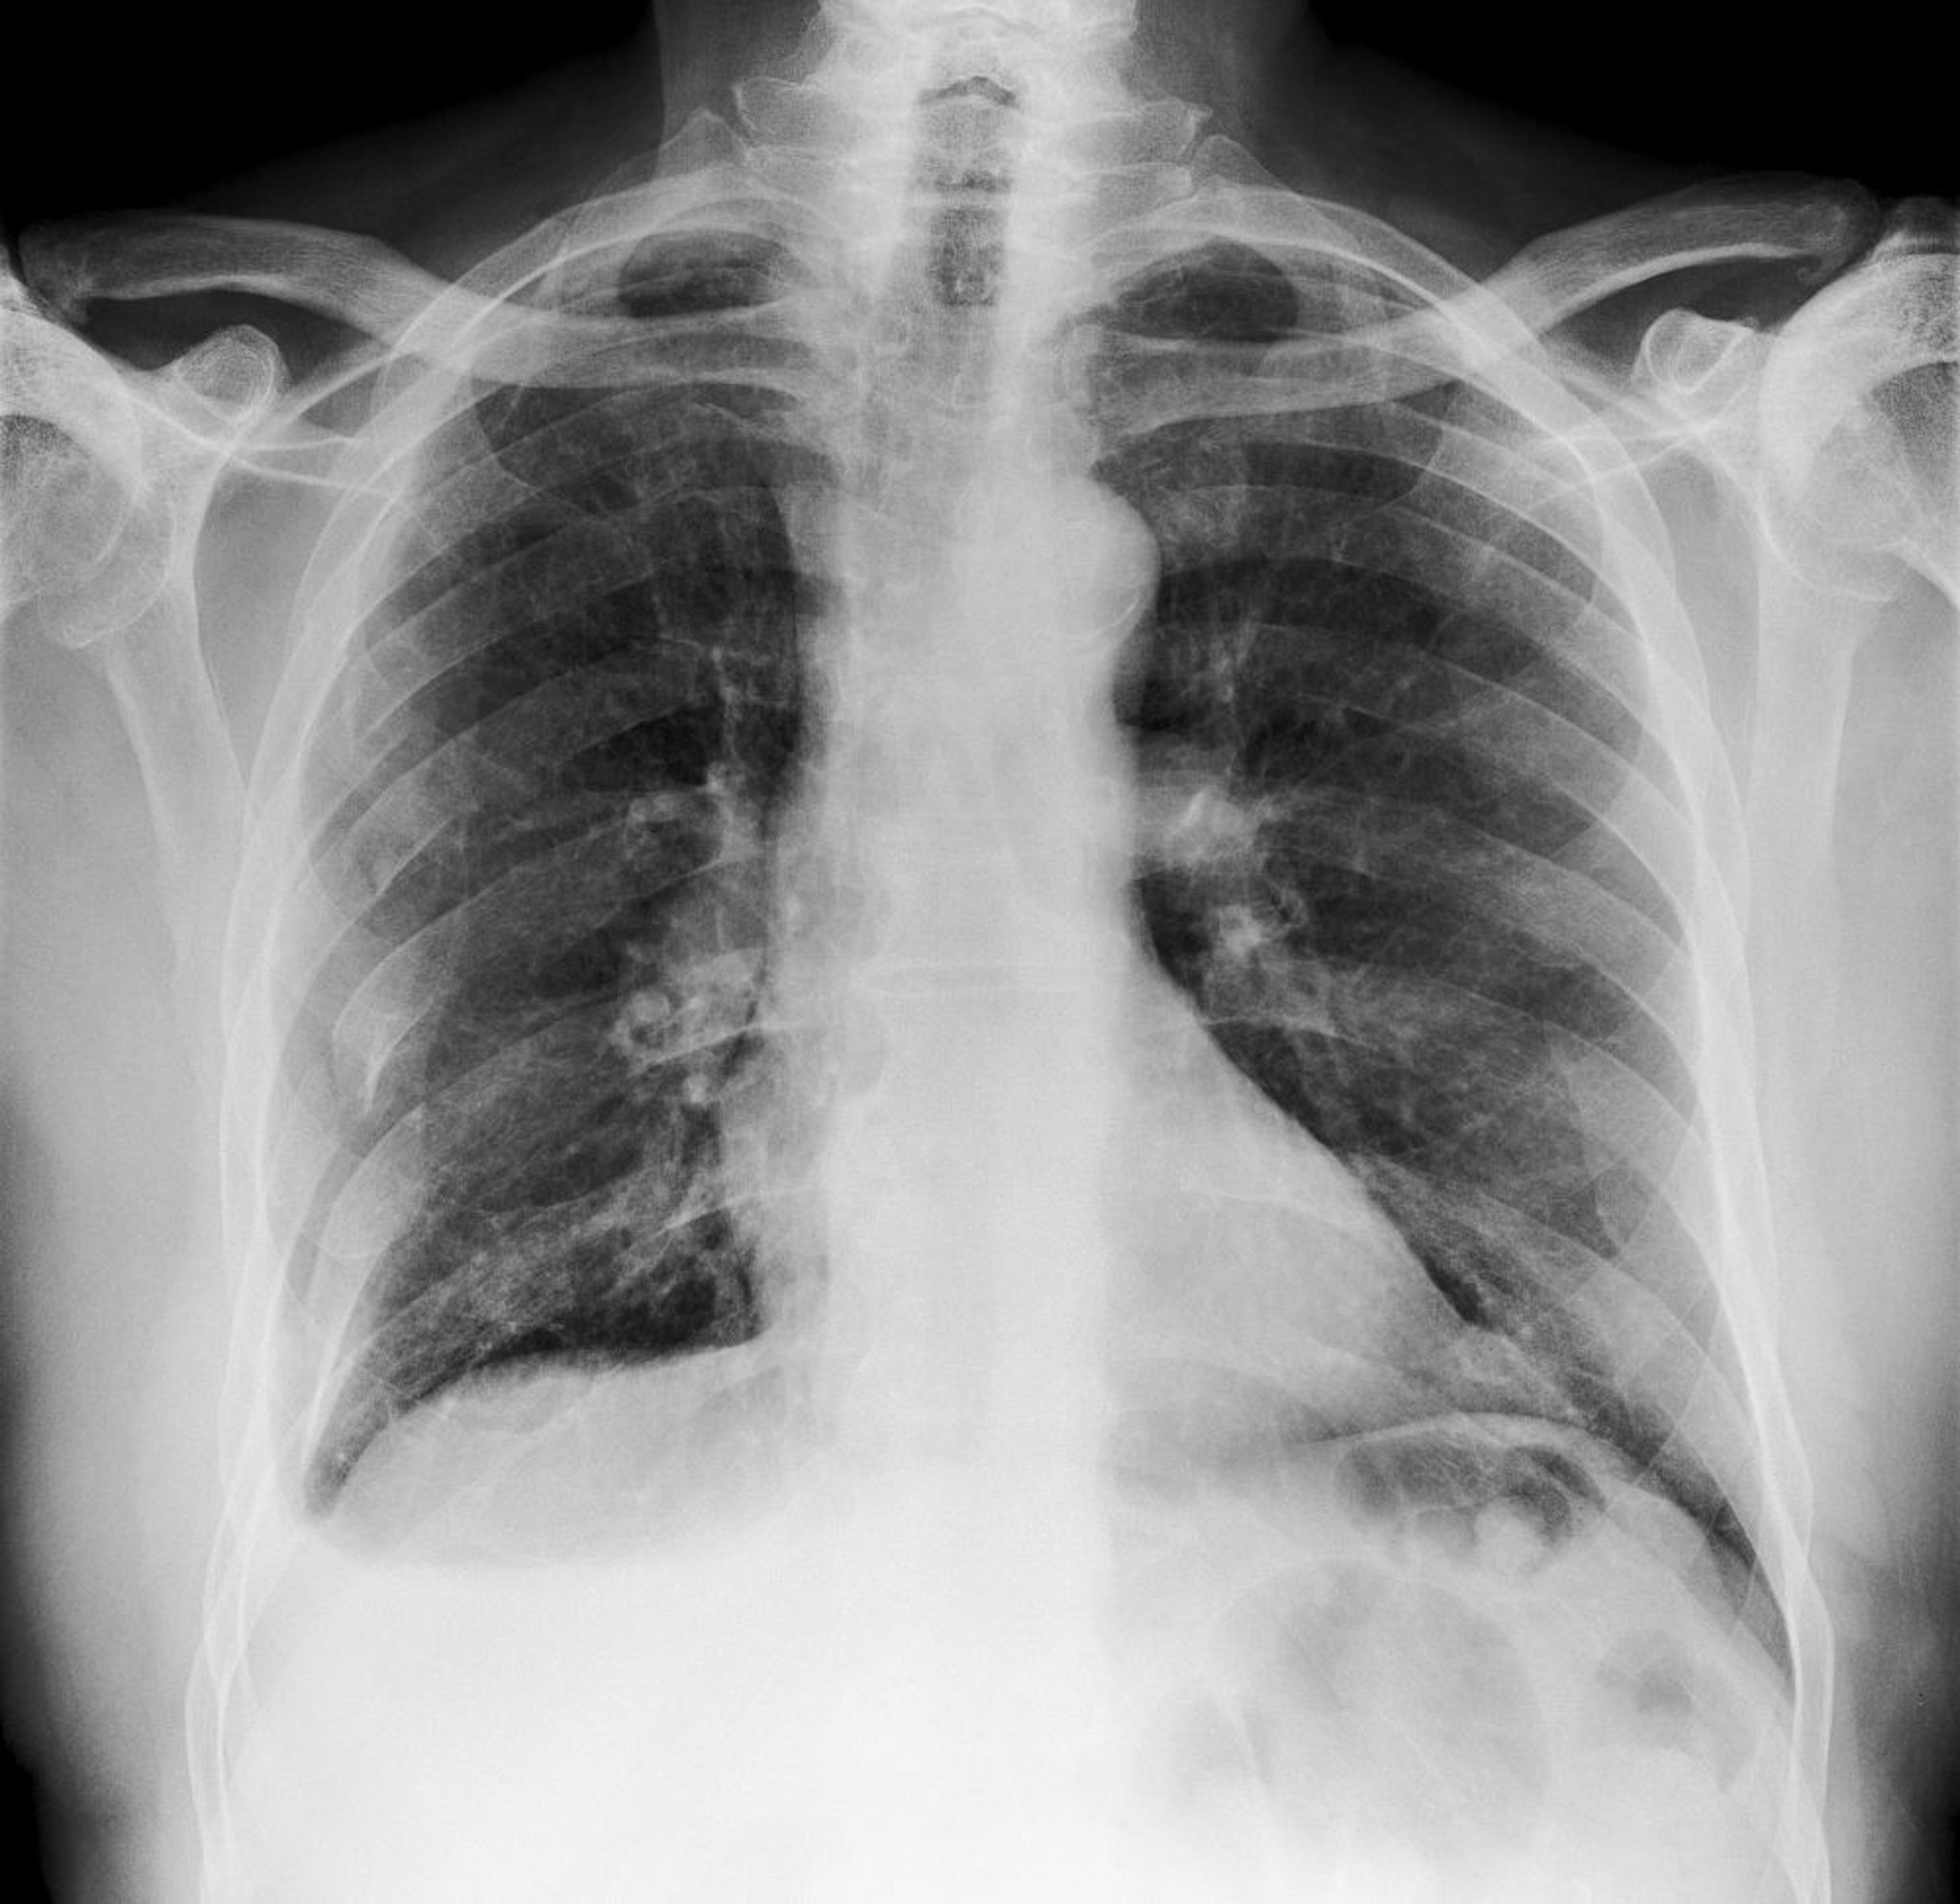

На цій рентгенограмі органів грудної клітки видно численні переломи правих ребер (помітні ліворуч).